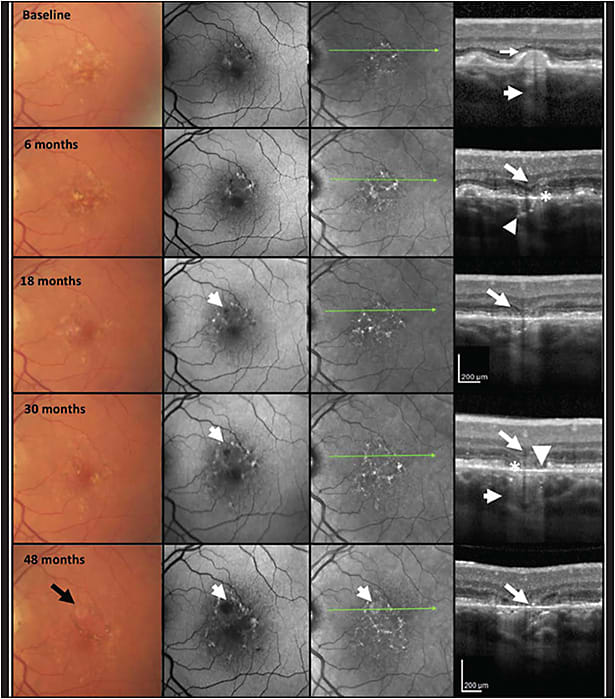

The CAM group defined macular atrophy by 3 main criteria on OCT: loss of the outer retina, loss of the retinal pigment epithelium (RPE), and choroidal hypertransmission. The latter 2 must be at least 250 μm in diameter (Figure 1).3 That number was chosen because we felt it was a size that could be reproducibly assessed by people who were reviewing the OCTs — namely, readers at a reading center.

As it has turned out, 250 μm works well as a cutoff for reproducibly identifying the lesions. The OCT correlate to the term geographic atrophy, which also is the OCT correlate for the more general term macular atrophy, is called complete RPE and outer retinal atrophy (cRORA). This term is defined by the above-mentioned 3 OCT criteria.

There is another term that is used when each of those 3 features are present, but do not meet the full criteria for GA or cRORA. This is called incomplete RPE and outer retinal atrophy (iRORA). These lesions may have some choroidal hypertransmission or disruption of the RPE, but they may not meet the full 250-μm threshold for cRORA. The lesions should have some degree of outer retinal atrophy as well.